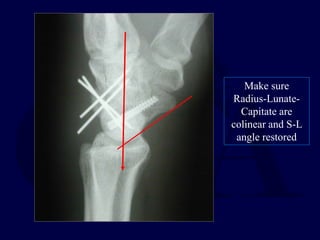

Make sure

Radius-Lunate-

Capitate are

colinear and S-L

angle restored